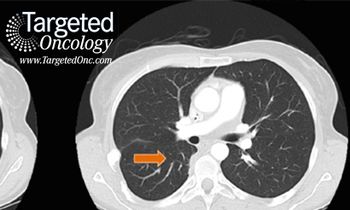

Treatment of certain head and neck cancers may soon be fundamentally transformed through the use of molecular diagnostics to dissect essential oncogenic driver pathways, and ultimately to identify targeted therapies that specifically inhibit them.